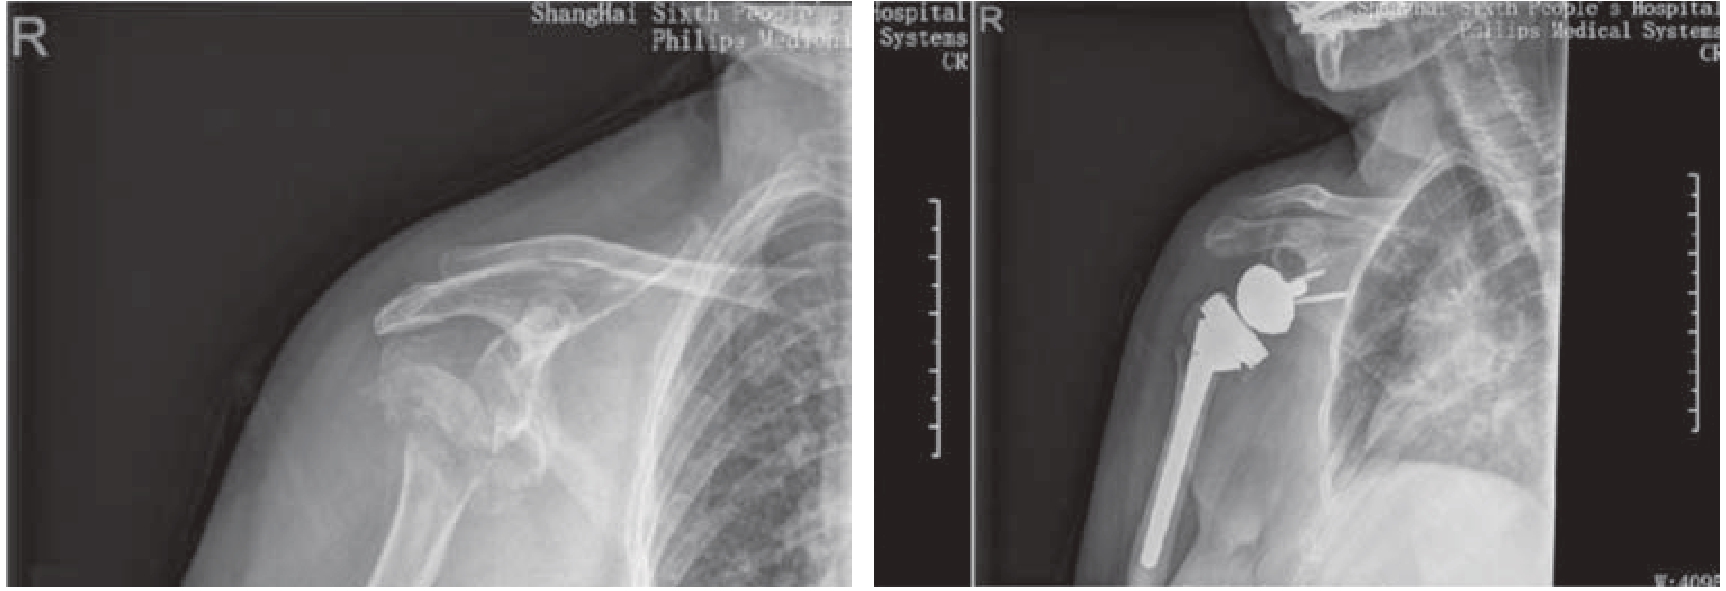

手术治疗的方案众多,包括闭合/切开复位钢板螺钉内固定、髓内钉内固定、经皮克氏针固定、经骨缝合固定以及肩关节置换等。目前应用最广泛的主要是锁定钢板固定、髓内钉固定和肩关节置换[7 11]。由于三部分、四部分骨折以老年骨质疏松性骨折多见,锁定钢板的角度稳定特性在骨质疏松骨折中能获得更好的把持力,降低复位丢失和固定失效的风险[12]。进行钢板内固定时,需要注意获得骨折的解剖复位,正确放置钢板,置入螺钉时避免穿透关节面,恢复或重建内侧柱支撑,肩袖行缝线张力带固定,使用结构性植骨或骨水泥加强骨质疏松骨(图3—3)、内侧皮质粉碎或嵌插骨折等骨量丢失骨折的固定等措施,以降低内固定失效等并发症的发生率[13 18]

img

图3—3 解剖型锁定钢板固定肱骨近端骨折,使用骨水泥加强骨质疏松骨的固定[14]